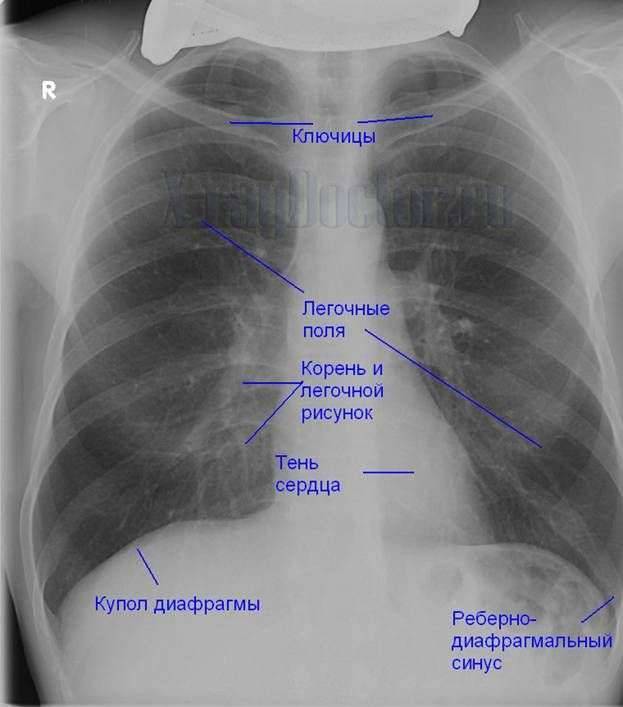

Снимок грудной клетки здорового ребенка: примеры и диагностика

Раздел: Мудрость в объективе